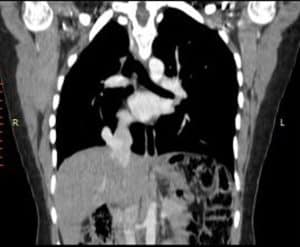

Investigations: Initial chest radiography revealed right lung volume loss and ipsilateral mediastinal displacement, raising suspicion for venous anomalies (Figure 1). A contrast-enhanced chest computed tomography (CT) scan was then performed, confirming the diagnosis of scimitar syndrome. The imaging demonstrated an anomalous right pulmonary vein draining into the IVC, associated with hypoplasia of the right lung (Figure 2, Figure 3, Figure 4). Additionally, two-dimensional transthoracic echocardiography was conducted to evaluate for any associated cardiac anomalies, which were not detected. An abdominal ultrasound was performed to assess liver size and anatomical relationships, yielding unremarkable results.

Figure 2: Chest CT

A linear scimitar shape opacity running from the midline of the lung toward the diaphragm (shown as arrow).